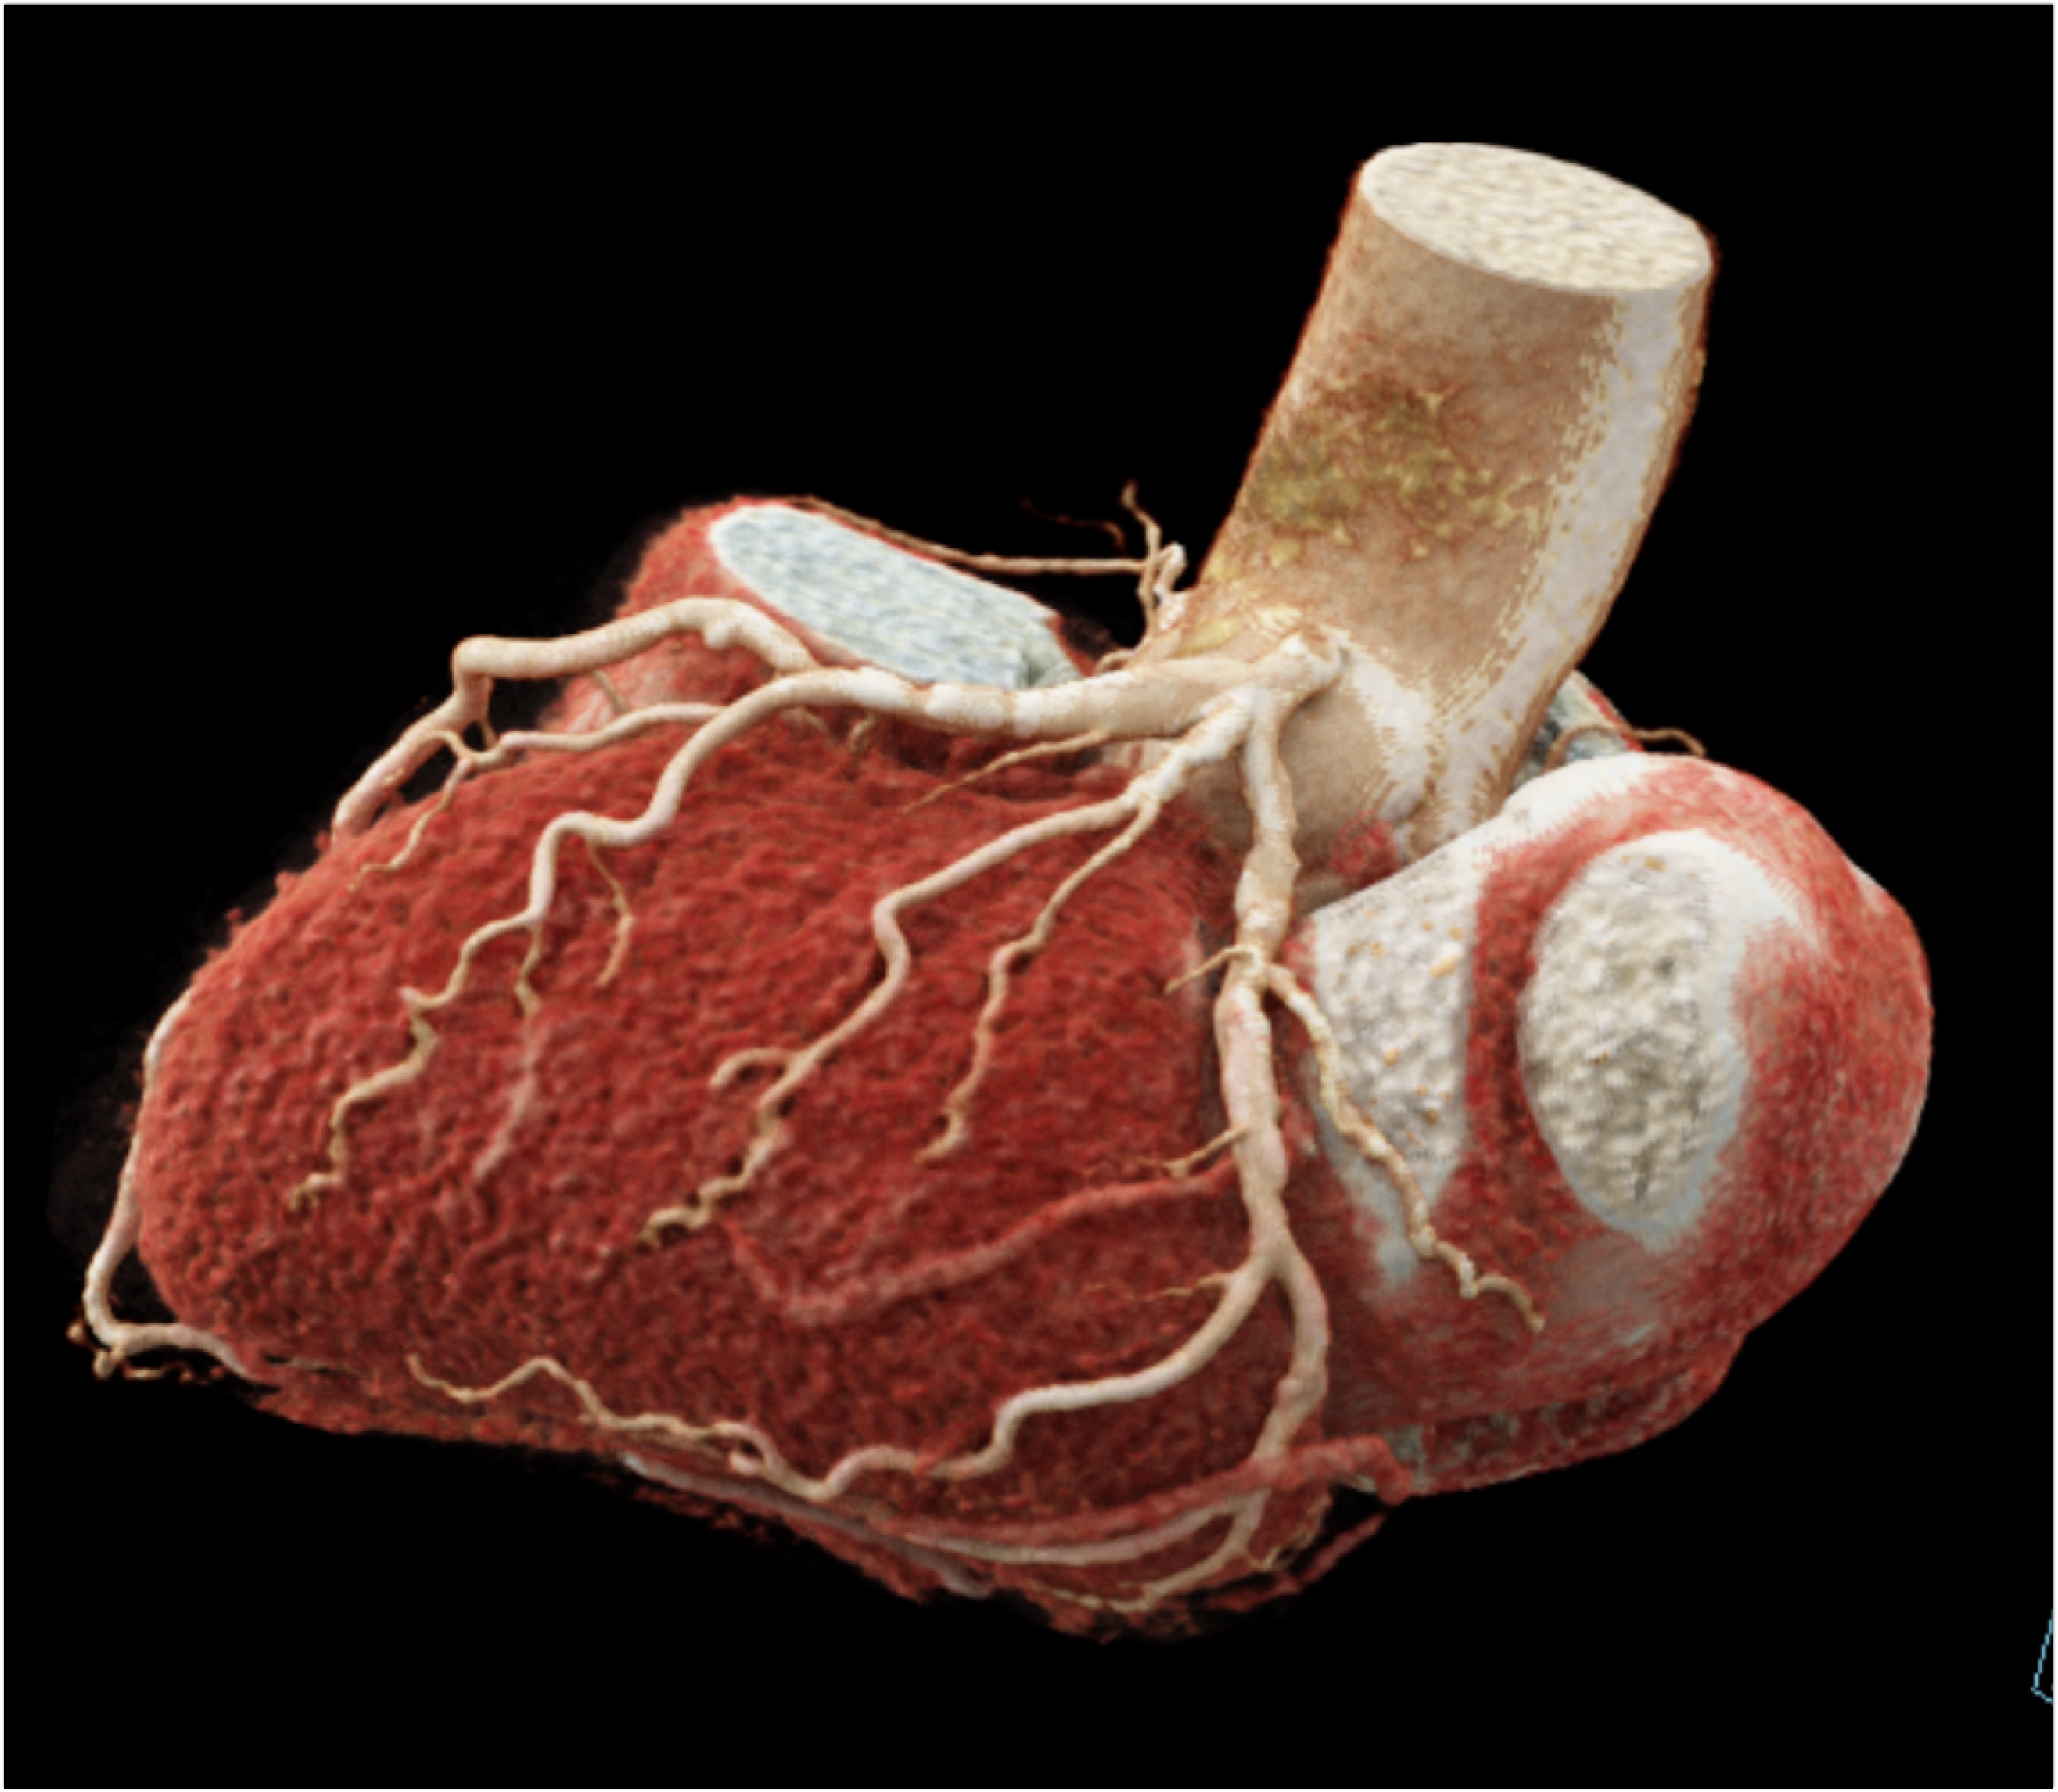

2) The vessel most involved with the coronary arterial disease is the

left anterior descending artery (LAD)

right coronary artery (RCA)

circumflex artery (Cx)

left main coronary artery (LMCA)